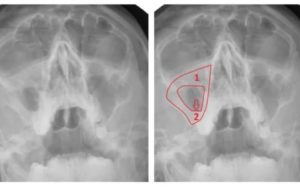

- Рентгенография. Самый популярный метод исследования околоносового пространства, позволяющий определить полноту воспалительного процесса, количество скопившейся в пазухах слизи, присутствие в носу полипов. ,

- рентгенография (снимок помогает рассмотреть назальные полипы);

- рентгенография;